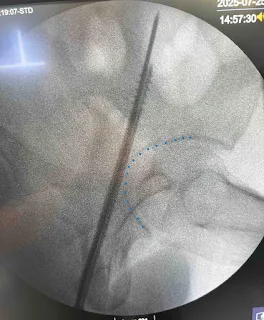

S1 Iliosacral screw (ISS) fixation : Technique

Dr. Sulabh Kumar Shrestha, MS Orthopedics, Mar 11, 2026Mar 11, 2026

Indications Entry point Anterior in S1 body and inferior to the overlapping iliac cortical density (ICDs) in true lateral projection Trajectory Dangers